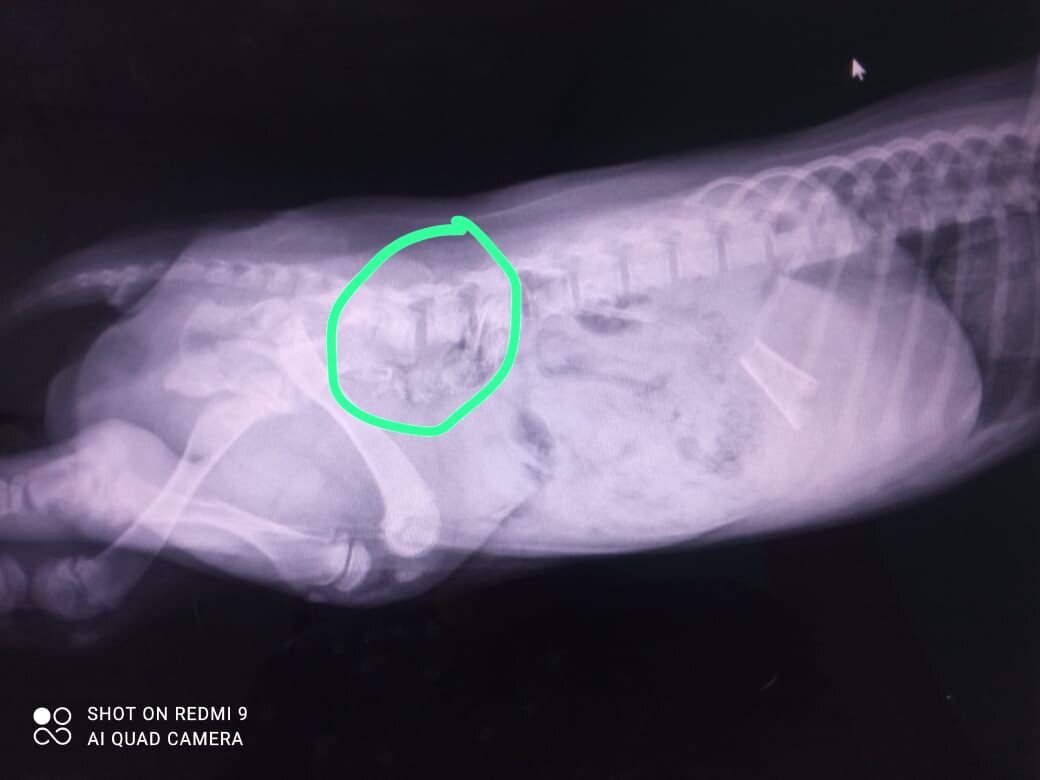

Кушать понемногу начала. Кости из желудка вышли естественным путем, слава Богу, не причинив ей вреда. Голди пыталась даже встать на задние лапки, поэтому решили переделать снимки и снять на рентген столе.

А теперь смотрите пока думали, что делать с позвоночником, позвонки сами встали на место!

Для врача это было также удивительное, как и для всех нас. Предновогоднее чудо! Позвоночник трогать не будем! Ну хоть что-то хорошее!